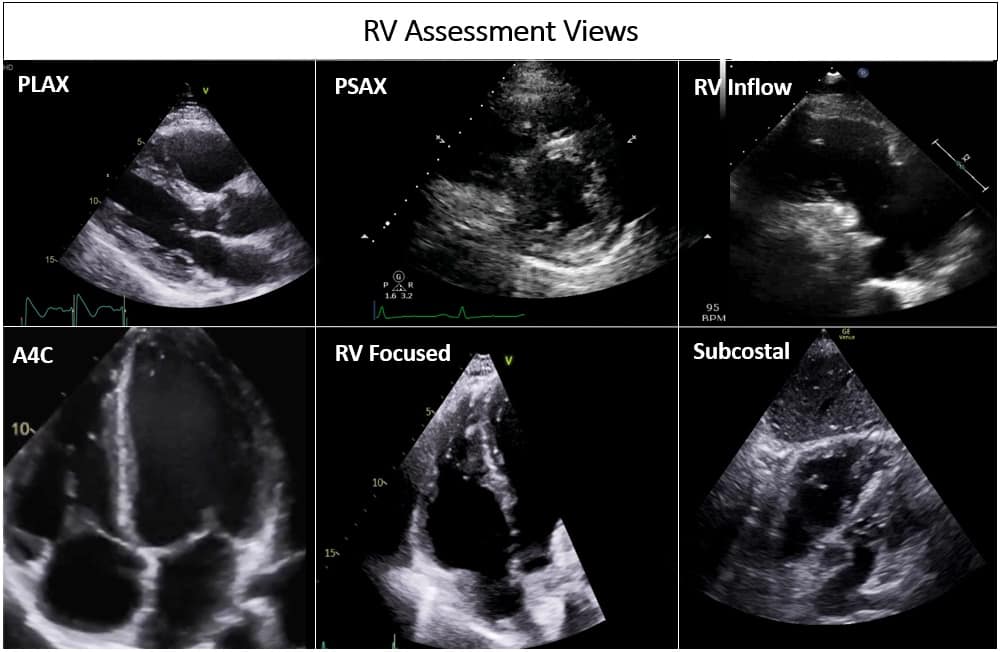

The crescentic shape of the RV wrapping around the left ventricle in a U-shaped manner implies that no single echocardiographic view completely encompasses the entire RV. Hence, a comprehensive echocardiographic assessment of the RV requires multiple windows. These include the conventional apical four-chamber (A4C), parasternal long-axis (PLAX) and short-axis (PSAX), RV inflow and subcostal views, and RV-focused view (Figure 1). On a transesophageal echocardiogram, the mid-esophageal four-chamber, RV inflow-outflow views, and the trans-gastric short- and long-axis views are utilized for RV assessment. Most RV dimensions and measurements are obtained in A4C, making it one of the most important views. A conventional A4C view is obtained from the cardiac apex to place the LV in the center of the screen. In this view, the RV-free wall may be obscured (Video 1). The RV-focused view is obtained by lateral displacement of the transducer to obtain the largest RV dimensions in the long axis (Video 2).7,8,10,11 Dimensions obtained in the RV-focused view significantly improve the accuracy of RV measurements.12 This is especially important in critically ill patients, where these measurements may be used dynamically to ascertain trends and responses to interventions. In patients on positive pressure ventilation, the parasternal and apical views may be difficult to obtain. One should be well-versed in utilizing the subcostal view to get a more reliable assessment of the RV in this patient population (Video 3).13

Figure 1: Different views assessing the right ventricle in transthoracic echocardiogram.

PLAX = parasternal long axis, PSAX = parasternal short axis, RV = right ventricle, A4C = apical 4 chamber